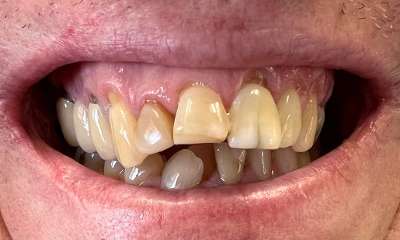

Crowns placed on front teeth to fix worn edges and darkening color of teeth. Crowns created harmony amongst the front teeth and gave the patient a more youthful smile.